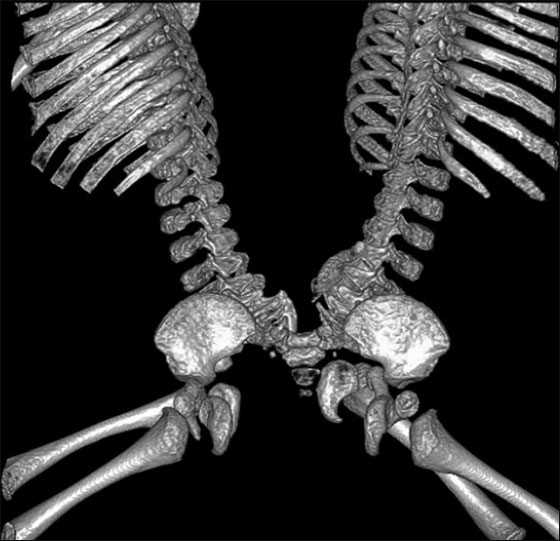

نجا توأمان سياميان بأعجوبة بعد عملية فصل بينهما، بعد ان كان عامودهما الفقريان ملتصقان طيلة فترة حمل والدتهما بهما، تضاف اليها ثمانية اشهر بعد ولادتهما، بحيث كانت فرصتهما للبقاء على قيد الحياة ضئيلة جدا. فتحدى التوأمان البالغان من العمر ثمانية اشهر كل الصعاب ونجيا من عملية فصلهما التي دامت 13 ساعة.

يواصل جشوا ويعقوب سابتيس من مدينة ممفيس بولاية تينيسي، صراعهما على الحياة تحت أعين الأطباء، لكنهما تغلبا على العقبة الأكبر ولم يبقى لهما سوى القليل. وقالت ادريان سابتيس والدة الطفلين، ان الأطفال على ما يرام منذ عملية الفصل بينهما، في 29 آب.

يعقوب لا يزال في العناية المركزة، ويحتاج الى القليل من العمليات الجانبية الاخرى، في حين أن جشوا هو خارج وحدة العناية المركزة، والان يستعد للعودة إلى المنزل. وافاد الدكتور ماكس لانجام، وهو احد الجراحين للتوأمين في مستشفى الأطفال "لو بونير" في ممفيس، تينيسي: "جشوا بحالة ممتازة، ونأمل ان يحظى بحياة طبيعية".